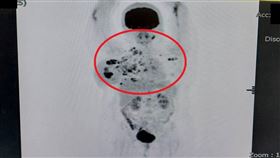

乳房紅腫熱痛誤為乳腺炎 檢查竟罕見乳癌

42歲的吳女士因右乳房突然腫脹疼痛且皮膚發紅,原以為...